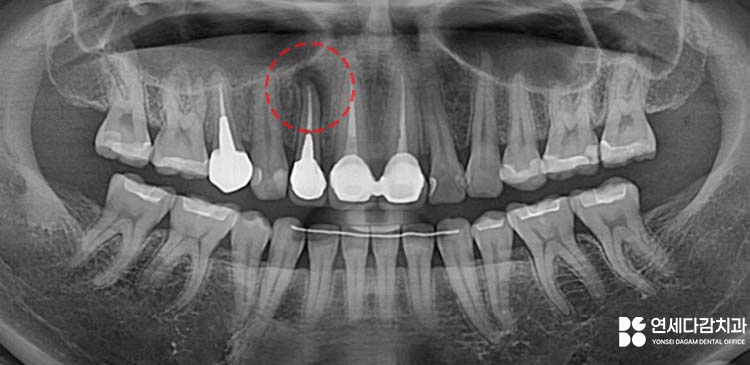

먼저 정확한 병소 위치를

파악한 후 잇몸을 절개합니다.

6개월 뒤 정기검진을 통해

가락동 치과 에서 파노라마

방사선 사진을 촬영하여 확인한 결과,

치근단 병소가 확연히 줄어든 것을

확인할 수 있었습니다.